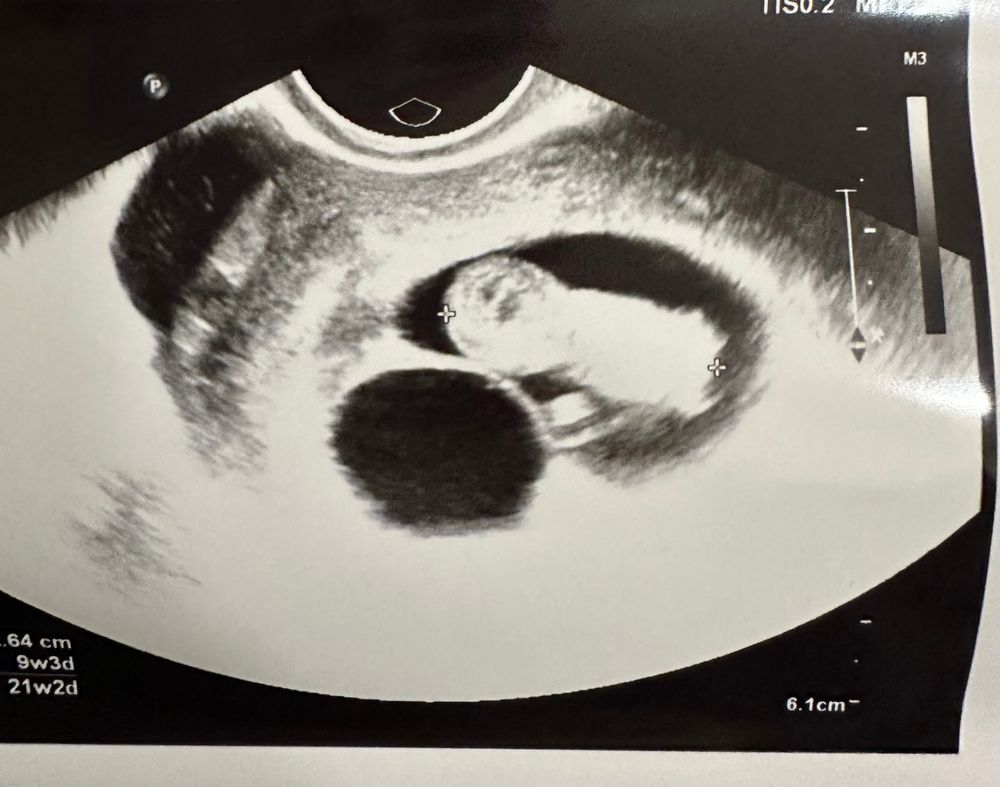

Но есть еще такой ракурс:

Я правильно понимаю, что это как бы сверху ракурс? И если смотреть отсюда, то место малышу есть?🥺

На втором снимке, судя по всему, вид сверху, и на нем как раз видно, что малыш как бы в узкой части ПЯ находится - на первом снимке, видимо, как раз этот «срез» сфоткали, если бы узист чуть правее посмотрела, там уже ПЯ в два раза шире. На мой дилетантский взгляд, все должно быть хорошо. Плюс замеры вроде по 4 сторонам всегда делают 🤔 даже фолликулов, яичников итд.. Лучше переделать узи, да, чтобы было спокойно.

Julia, вы представьте в объеме это ) там есть достаточно места . Если бы сверху мало было бы , другой вопрос , а так малыш может крутится куда хочет 😃